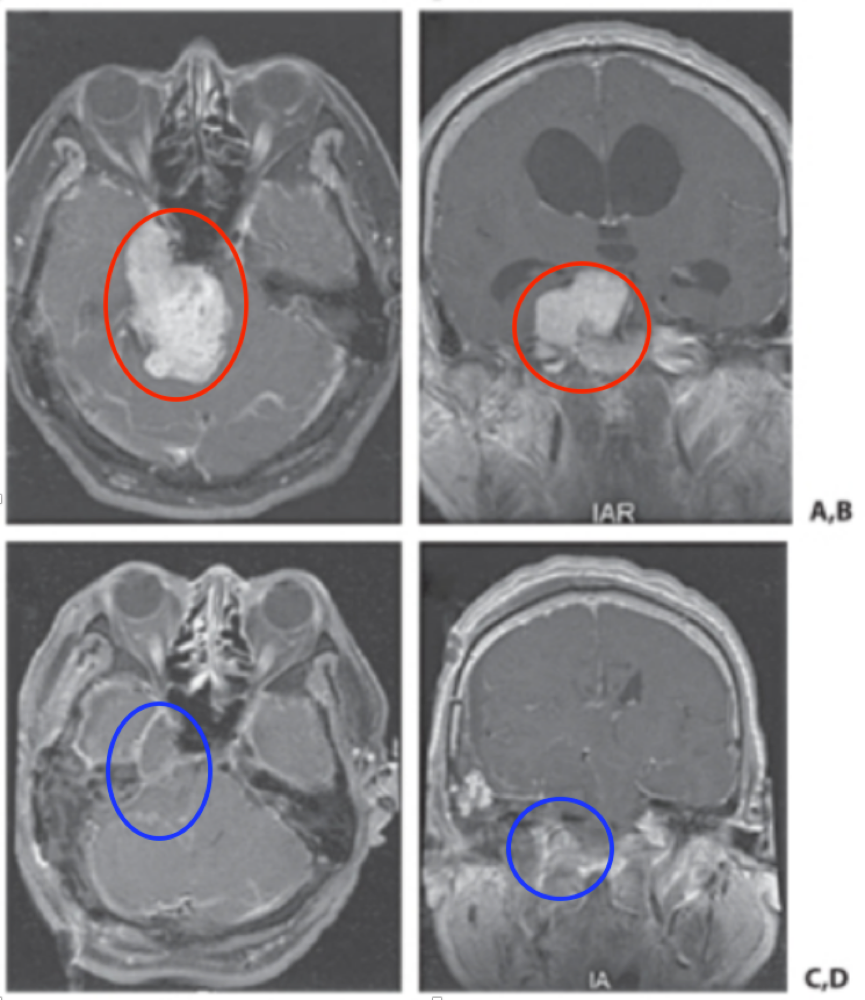

神经鞘瘤是起源于神经鞘的雪旺细胞的良性肿瘤。它们可以起源于任何外周神经、颅神经或自主神经。三叉神经鞘瘤少见,占全部颅内肿瘤的0.07-0.3%,占颅内神经鞘瘤的0.8%-5%。它们可能...

三叉神经鞘瘤是比较常见的非前庭神经鞘瘤,占颅内神经鞘瘤的1 ~ 8%,占颅内肿瘤的0.1 ~ 0.5%。常常发生在中年人身上,也可以发生在任何年龄,包括儿童。三叉神经鞘瘤可以发生在三叉...